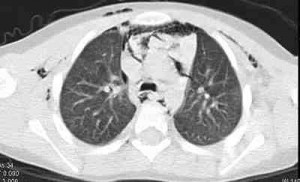

Se encontraba hemodinámicamente estable, con saturación periférica de oxígeno de 95%, eupneico y sin signos de dificultad respiratoria. En la observación se objetivó crepitación cervical y de la pared torácica anterior; la auscultación pulmonar reveló murmullo vesicular globalmente disminuid, con sibilancia dispersa e incremento del tiempo espiratorioHa realizado radiografía (ver Figura 1) y tomografía computarizada (TC) torácicas (ver Figuras 2, 3, 4 y 5), identificándose enfisema subcutáneo y neumomediastino extensos, neumotórax y aire ectópico en la región retrocrural y gotera paravertebral izquierda. Comenzó oxigenoterapia por máscara de alto débito, broncodilatador nebulizado y corticosteroide sistémico, mejorando clínicamente y radiológicamente en 5 días. A los 12 meses de seguimiento el niño está asintomático y sin recidivar.

Figuras 2, 3, 4 y 5. Tomografía computarizada torácica demostrando enfisema subcutáneo (flechas blancas), aire en el mediastino superior y anterior (*), pequeño neumotórax (flecha negra) y aire ectópico en la gotera paravertebral izquierda (+).